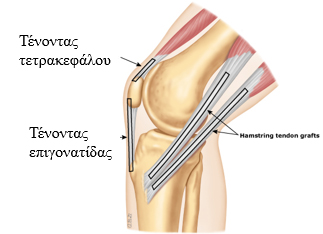

Η χειρουργική αντιμετώπιση της ρήξη προσθίου χιαστού περιλαμβάνει την ανακατασκευή του συνδέσμου με την χρήση ενός μοσχεύματος.

Το μόσχευμα αυτό λαμβάνεται από τον ίδιο τον ασθενή (αυτομόσχευμα) και μπορεί να είναι κομμάτι του τένοντα της επιγονατίδας ή οι τένοντες από δύο μύες που βρίσκονται στην οπίσθια πλευρά του μηρού (ισχνός και ημιτενοντώδης). Πιο σπάνια λαμβάνεται κομμάτι του τένοντα του τετρακεφάλου.

Η επέμβαση γίνεται αρθροσκοπικά δηλαδή εκτός από την τομή για την λήψη του μοσχεύματος, γίνονται δύο οπές στο γόνατο. Δια μέσω αυτών εισάγεται μία κάμερα στην άρθρωση και τα εργαλεία που επιτρέπουν την τοποθέτηση του μοσχεύματος στην καταλληλότερη θέση. Η όλη διαδικασία παρακολουθείται σε μία οθόνη υψηλής ευκρίνειας.